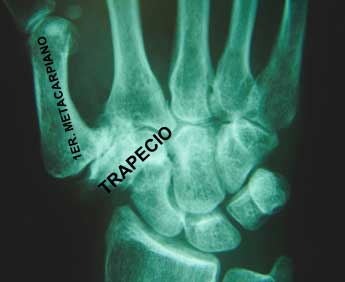

La Rizartrosis, o artrosis de la raíz del pulgar, es la lesión degenerativa más frecuente en la mano debida al desgaste progresivo de la articulación entre el trapecio y el primer metacarpiano.

Radiológicamente, el espacio entre el trapecio y el metacarpiano ha disminuido.

Dependiendo del grado de evolución de la rizartrosis, esta disminución del espacio articular puede evolucionar desde un ligero “pinzamiento” hasta una completa destrucción de la articulación.

- Radiografía: Permite visualizar el grado de desgaste articular, estrechamiento del espacio articular y deformidades óseas.